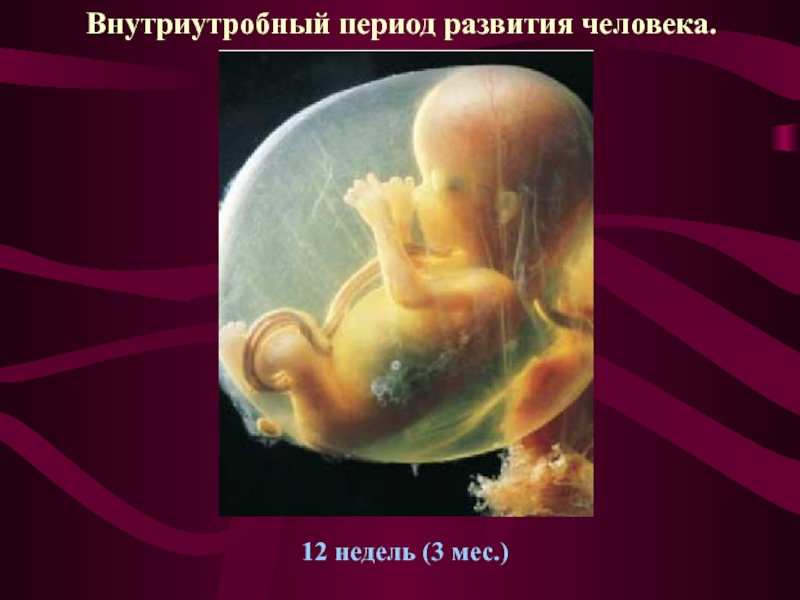

Этапы развития эмбриона человека: 14 недель